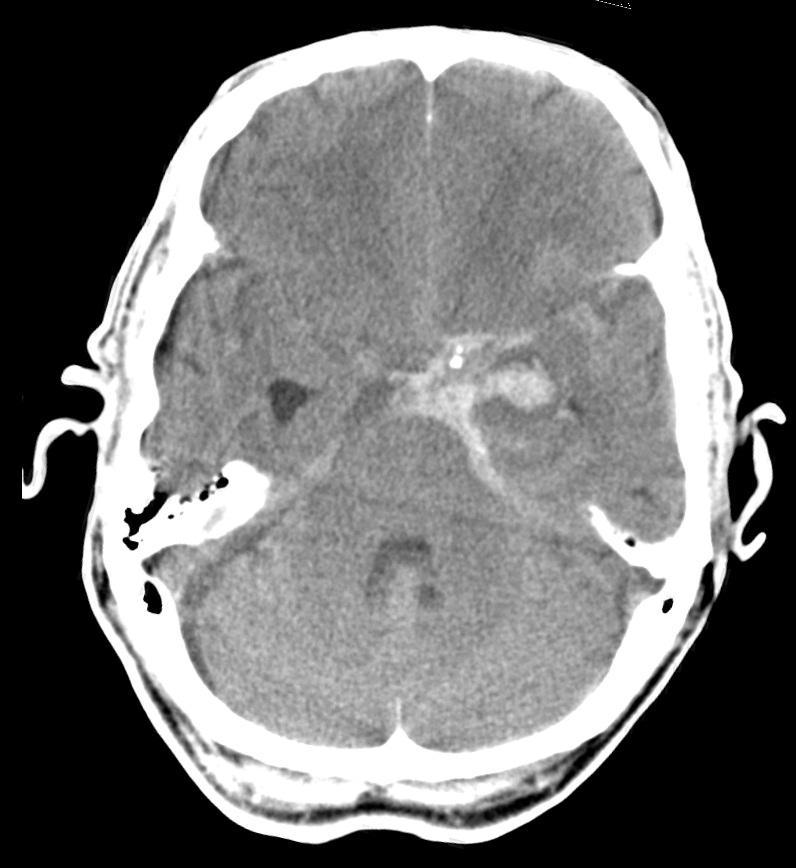

Subarachnoid Haem